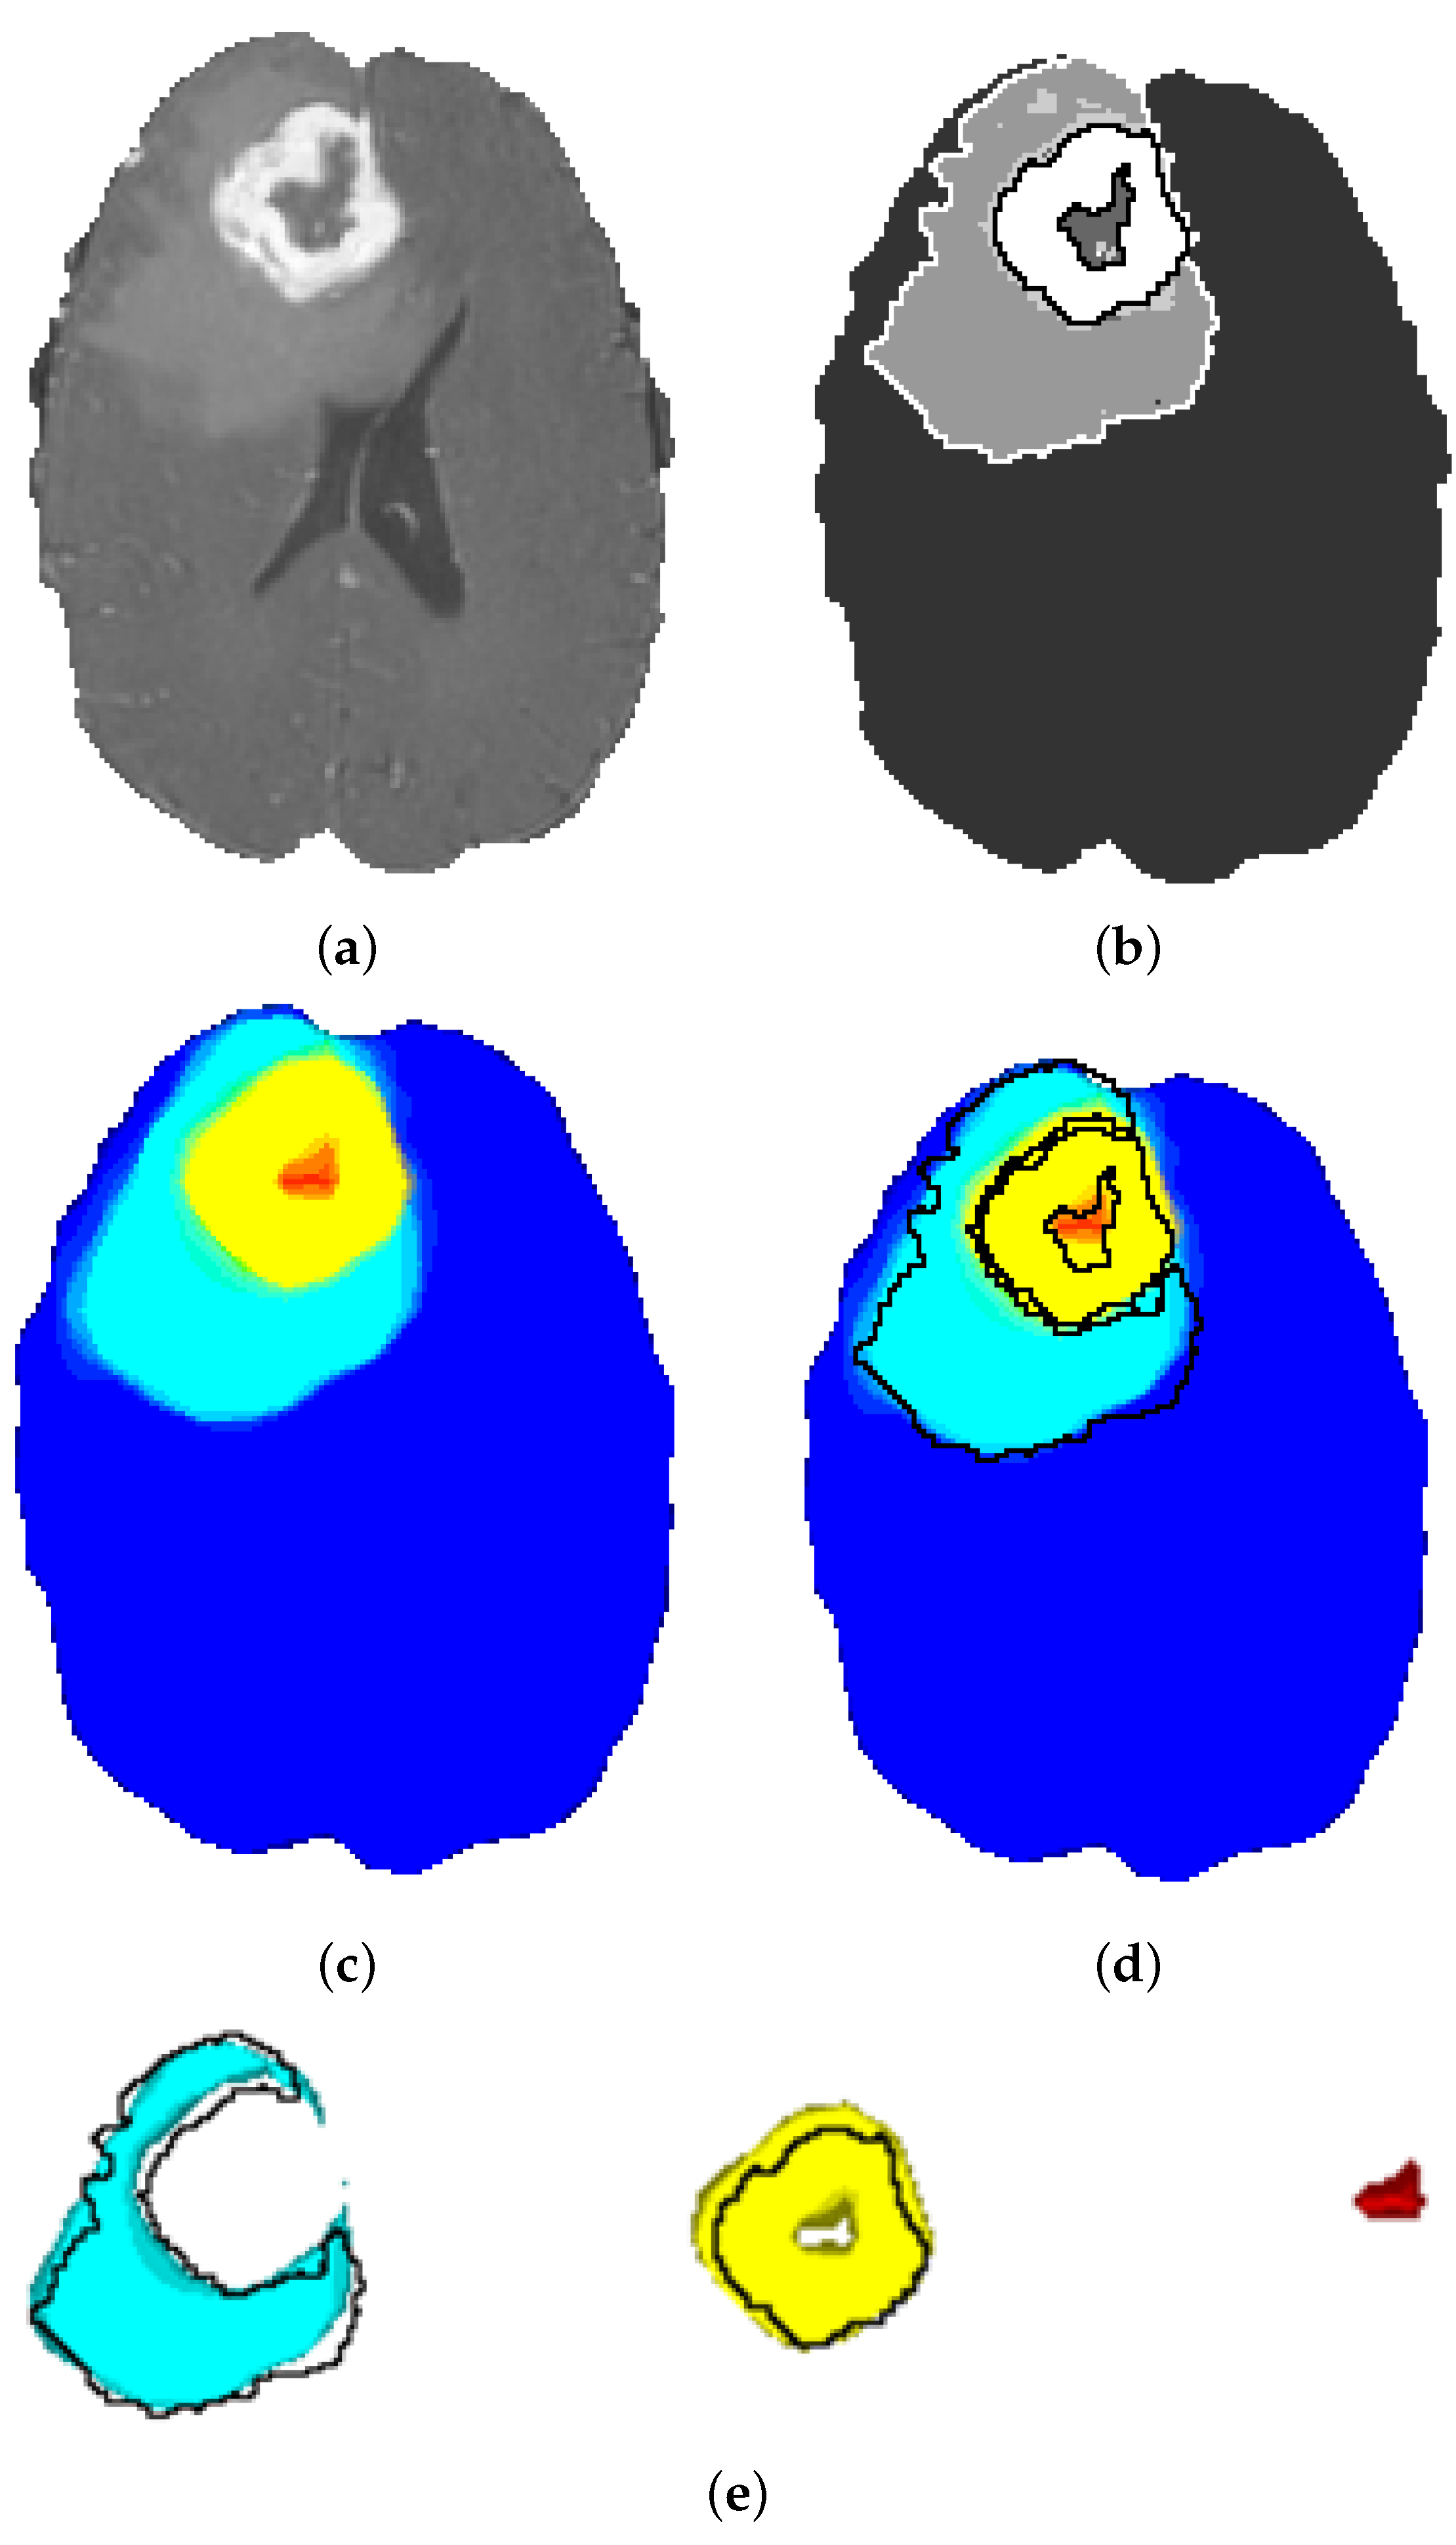

The segmentation maps obtained by the ensemble model are depicted in Figure 12. It is obvious that the tissue contours and transitions from one tissue to the other are gradually colored from turquoise to yellow, and there is a slight green ring at the transition. This shows that the ensemble model obtains a probability map and does not make a final decision favoring any class for uncertain tissue voxels on the contour. These voxels are, in fact, the hard examples and are not clearly classifiable. The probabilistic heatmap of the ensemble model solves this problem through probabilistic voting.

Figure 12. Segmentation Results of the Ensemble Model: (a) original image; (b) ground truth with annotation contours; (c) ensemble segmentation; (d) ensemble segmentation with annotation contours; (e) ensemble segmentation of ED (turquoise), AT (yellow), NEC (red), Annotation Contours (black).